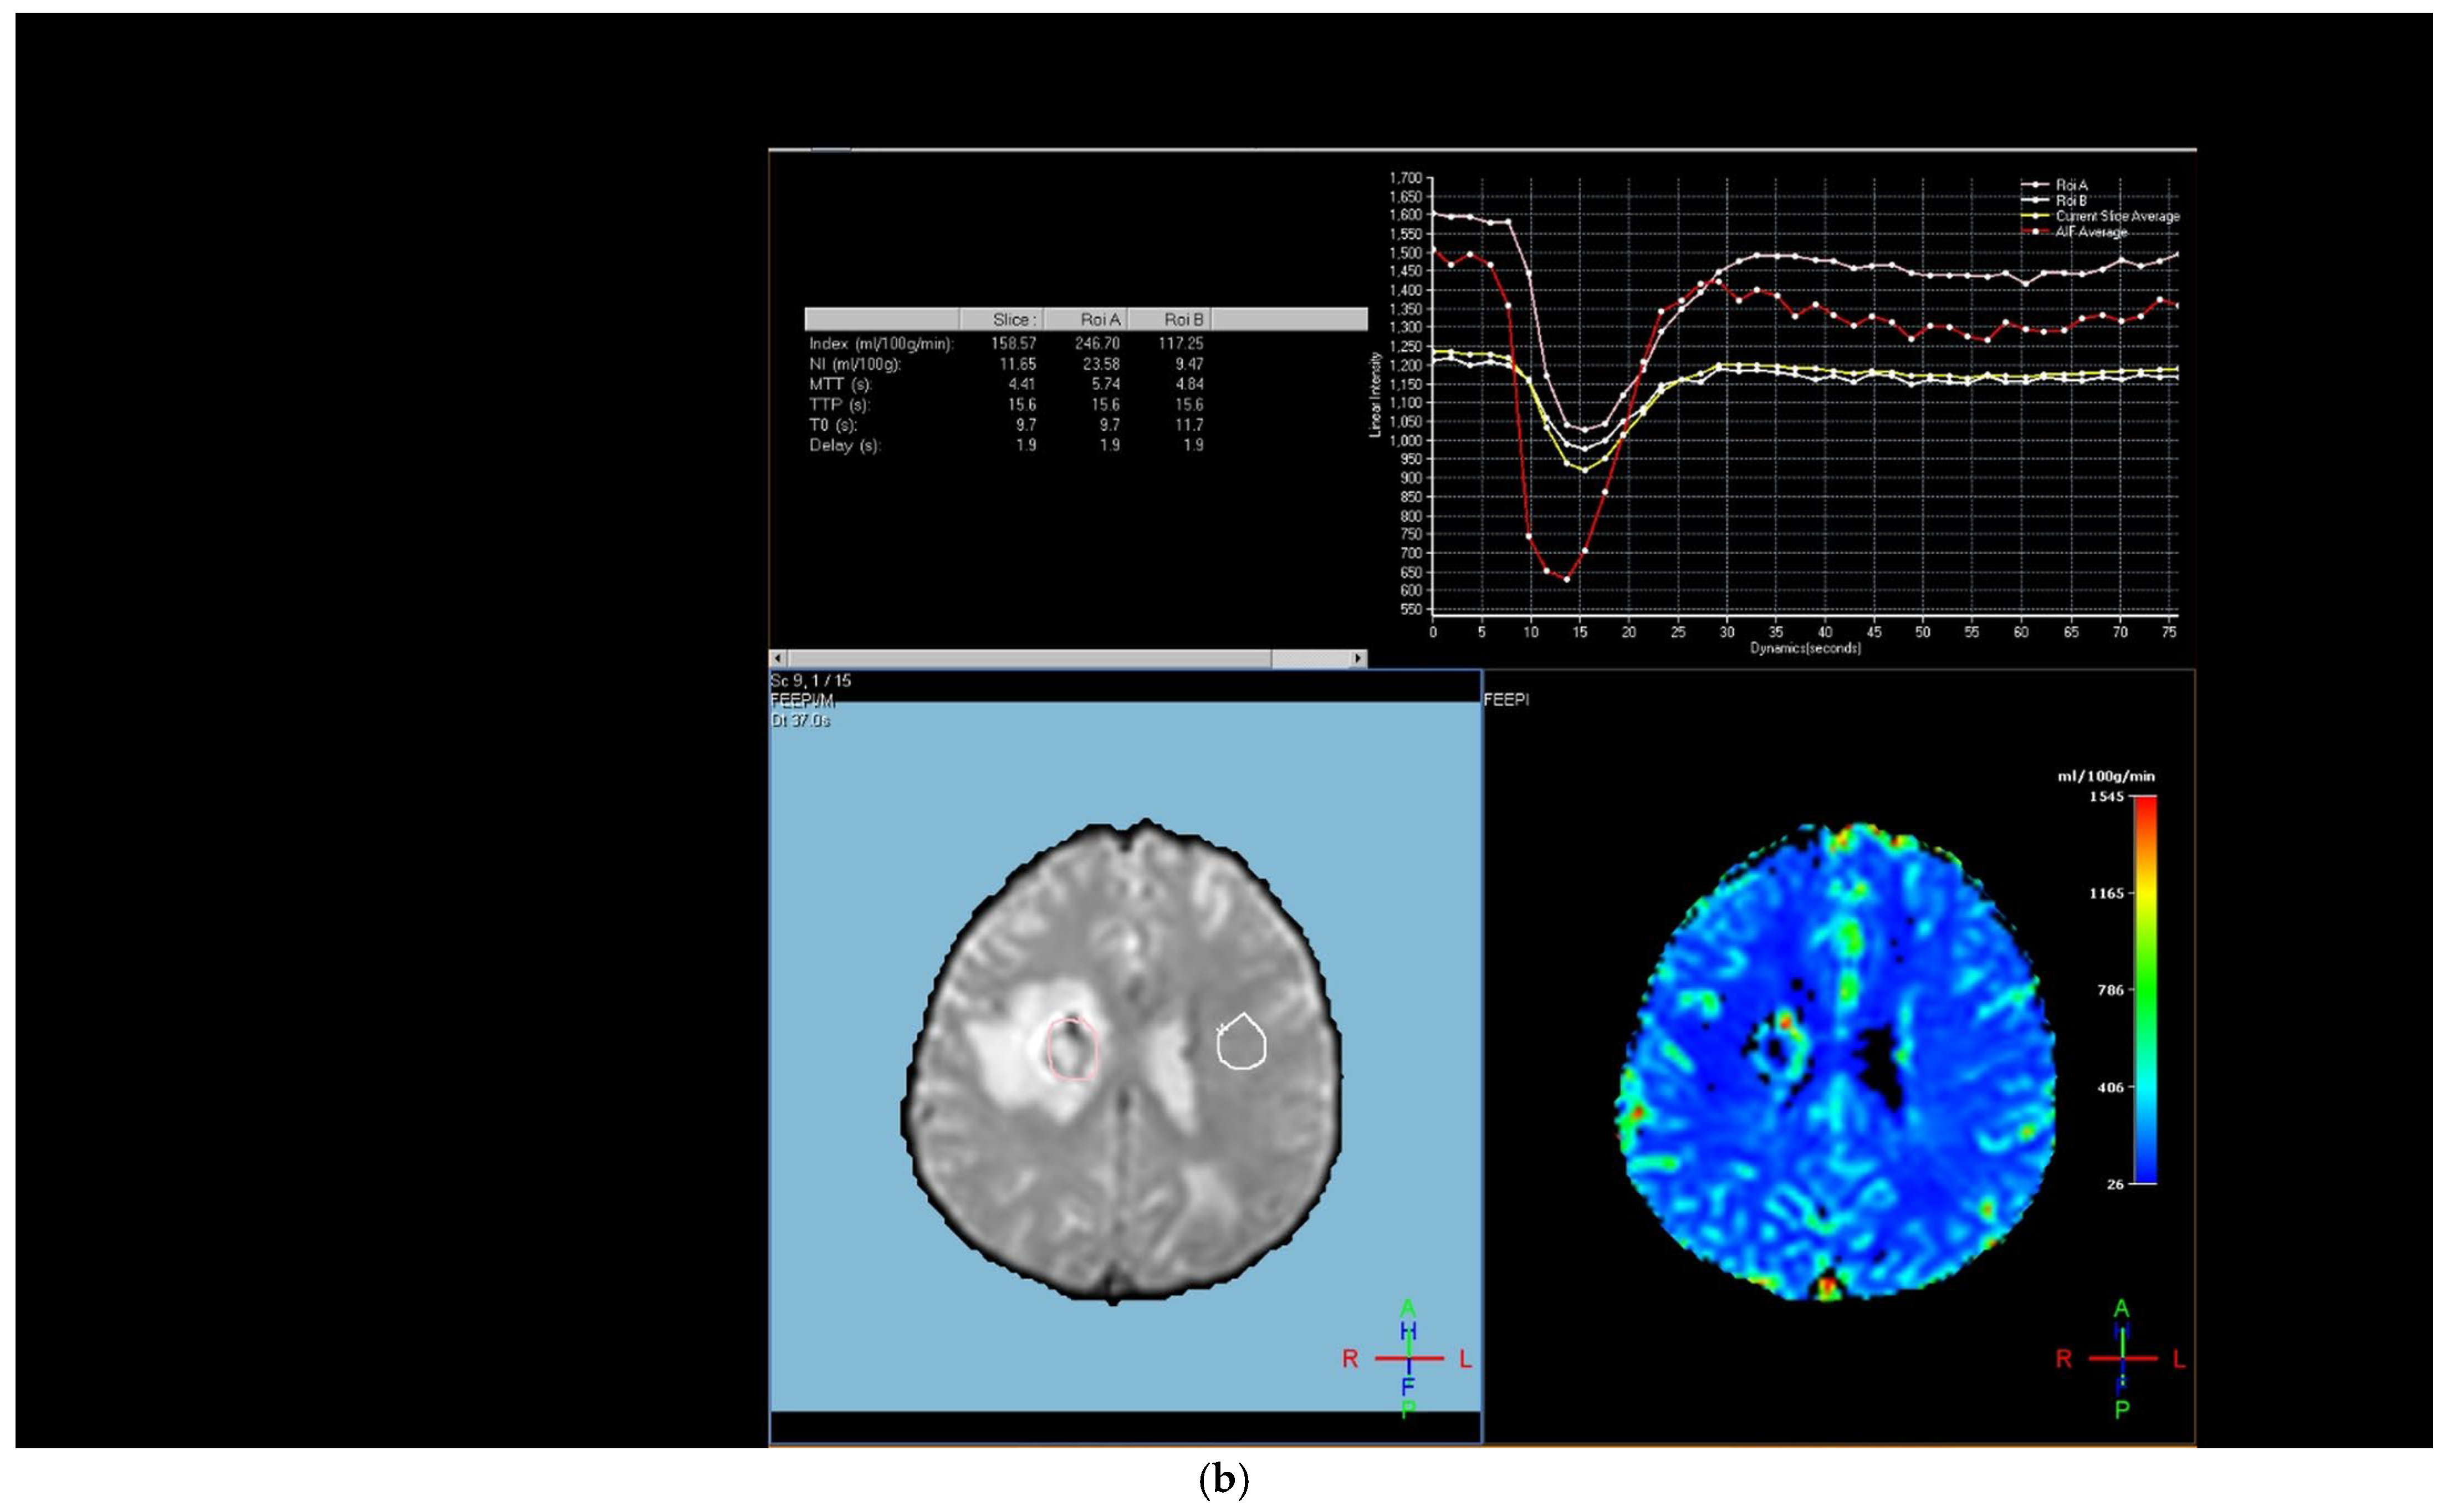

Table 4 shows the results of ROC analysis for tumoral rCBV and peritumoral rCBV in differentiating high-grade glial tumors from brain metastases in patients. The AUC value for tumoral rCBV was 0.816 (95% CI: 0.720–0.890; p < 0.001) and for peritumoral rCBV was 0.725 (95% CI: 0.620–0.814; p = 0.003) in differentiating high-grade glial tumors from brain metastases (Figure 4). According to the Youden index, the optimal cut-off point for tumoral rCBV was >1.339 (sensitivity: 87.5%, specificity: 73.85%) and for peritumoral rCBV was >1.238 (sensitivity: 58.33%, specificity: 90.77%).

Figure 4. Receiver operating characteristics curve for relative cerebral blood volume values in differentiating high-grade glial tumors from brain metastases (n = 89).